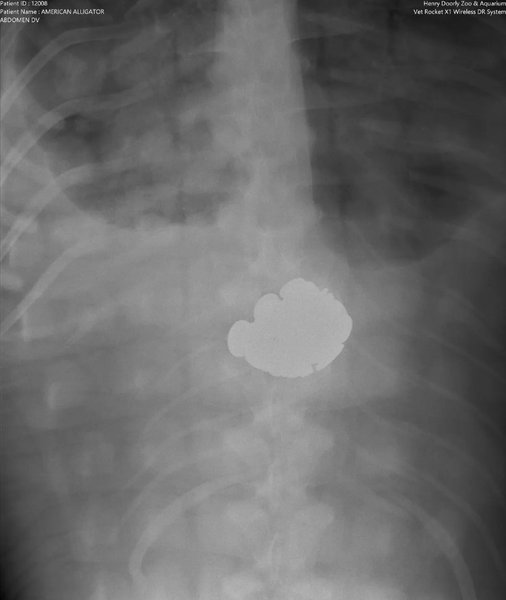

Во время одной из таких проверок ветеринары обнаружили нечто удивительное в желудке 36-летнего аллигатора-лейциста (Alligator Mississippiensis): команда обнаружила в брюхе хищника 70 монет Соединенных Штатов Америки.

аллигатор тибодо монеты

В желудке аллигатора обнаружили 70 монет